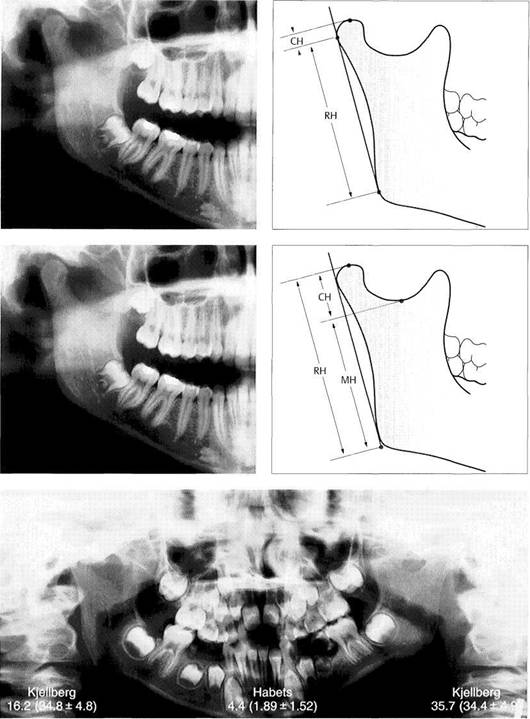

Panoramic radiographs produce an 18-21% magnification in the vertical direction (Larheim and Svanaes 1986). The dis­tortion is even greater when the patient is positioned incor­rectly (Tronje et al. 1981). In 1988 Habets and coworkers first proposed a method for determining asymmetries on a panoramic radiograph. Various investigators have used this asymmetry index (AI) in clinical studies (Athanasiou 1989, Bezuur et al. 1989, Schokker et al. 1990, 1994, Miller 1994, Miller et al. 1994).

The principle behind this index is that the vertical heights of the right and left condyle and ramus are measured on a

panoramic radiograph and these values are used in the for­mula AI = [(R-L)/(R+L)] x 100% to calculate the asymmetry index. This is calculated separately for the heights of the condyles and the rami. But as demonstrated in studies by Turp et al. (1995, 1998) and by Ferrario et al. (1997), any conclusions reached by employing the asymmetry index are unreliable.

Kjellberg et al. (1994) presented a method to be employed unilaterally on each side to eliminate errors caused by mag­nification.

378 Habets, asymmetry index

This asymmetry index (Al) is calculated from the formula Al = [(R-L)/R+L)] x 100% in which R and L stand for the values on the right and left sides. Al can be calculated for either the height of the condyle (CH) or of the ramus (RH). A differ­ence of more than 3% indicates an asymmetrical relationship. Errors can arise, however, through devia­tions in the projection angle or po­sitioning of the patient, and these reduce the reliability of the results (Ferrario et al. 1997, Turp et al.

Kjellberg's asymmetry

index

This determination uses other ref­erence points. By calculaing the quotient of CH:MH or CH:RH in the comparison of the two sides, the magnification error is avoided. The normal values for CH:MH and CH:RH are approximately 35 and 53 respectively. Comparison of the quotients for the two sides allows one to draw a conclusion about asymmetrical relationships in the ascending rami.

CH condyle height

MH         mandible height

RH ramus height

Asymmetry indices for a

patient with hypoplasia of the

right condyle

Comparison of Kjellberg's unilateral index (right and left values with nor­mal values in parentheses) and Ha-bets' asymmetry index (central fig­ures). Even though in this obvious clinical example the values point in the right direction, the clinical sig­nificance of these, and the asym­metry index in general, is very questionable because of the bio­logical variations in condylar form (Ferrario et al. 1997) and length (Turpetal. 1998).